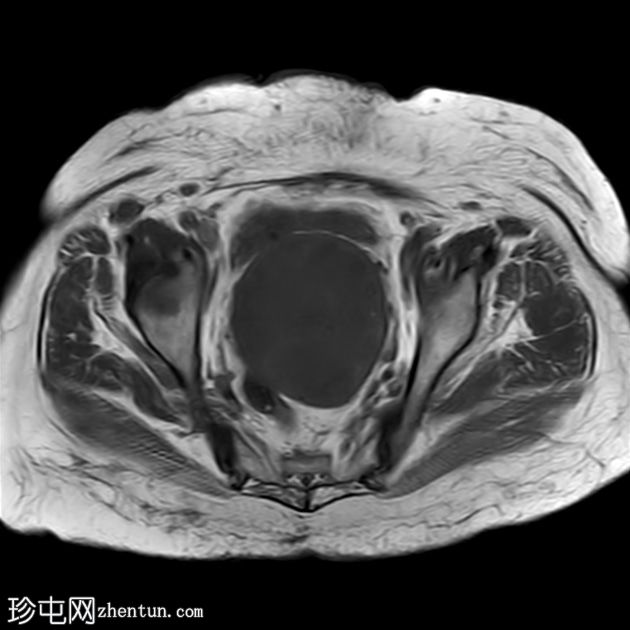

轴位

T2

2.jpg

子宫呈U形,宫底轮廓消失,宫底突出至扩张的阴道内,宫颈位于内翻的宫底上方(II级子宫内翻):

宫底处可见阴道内可见边界不清、分叶状实性肿块,明显扩张阴道壁,阴道壁完整。

肿块最大轴向及头尾径约为 9.7 x 9.6 x 9.5 cm,T1 加权像呈低信号,T2 加权像呈中/高信号,伴有扩散受限和不均匀增强。

肿块前方压迫膀胱,后方紧邻乙状结肠,未见侵犯。

轴位MRI:可能显示靶环状或同心环状结构,提示子宫内膜存在不同层次。